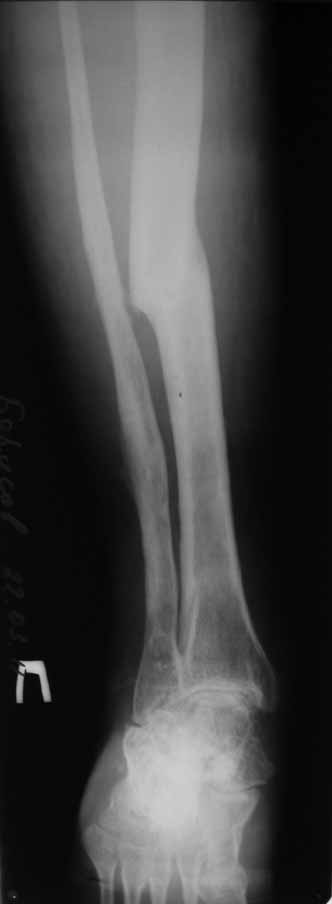

В анамнезе этапные операции по поводу устранения Coxa Vara, формирование артродеза коленного сустава, удлинения бедра. В данный момент беспокоит укорочение 7 см, эквинус стопы. Объективно: - местный статус виден на фото, сосудистых и неврологических расстройств нет. Обратился в консультативном порядке, настроен на удлинение голени в г.Волгограде. (со слов больного - не берут без санации очага на голени). Ваши предложения? Из кулуарных соображений - а не актиномикоз ли это? Иссечение рубцов+ VAC+ Стержень с аппаратом + микрососудистый трансплантат(?)

Ваш вопрос, коллега, вполне правомерен. В советское время те из нас, кто занимался костно-гнойной инфекцией видели достаточное количество подобных несчастных, кочующих из стационара в стационар. Своеобразный госпитализм приводил к тому, что люди тратили всю свою, как правило достаточно короткую жизнь, на лечение зачастую реально неизлечимых процессов. В данном случае имеющаяся рентгенологическая картина груботрабекулярной перестройки кости, сочетающаяся с участками склероза говорит, скорее всего, о том, что вся имеющаяся картина, дополненная чудесными фотографиями,вполне укладывается в клинику гематогенного остеомиелита, которым и страдает пациент с детства. Никакие санации, к сожалению, не приведут в данном случае к излечению, так как все имеющиеся рубцы являются зоной жизни этой самой инфекции. При продолжении лечения не исключено достаточно раннее развитие амилоидоза в этом случае. Мне кажется, что оптимальным было бы определить пациента в институт протезирования и протезостроения или в то учреждение, которое в регионе выполняет данную функцию. Специалисты помогли бы определиться с уровнем ампутации, являющейся, по сути, единственным способом разорвть порочный круг и дать пациенту возможность какой-то социальной адаптации. А в плановом порядке, насколько мне известно, можно добиться неплохого финансового обеспечения под протез конечности по квоте. Другого решения здесь нет. С уважением, Андрей Волна

извините за очепятку - не берут без санации очага на бедре. Сейчас имеется отделяемое из нижнего свища с периодическим выходом секвестром в виде мелкой крошки. Движений в ТБС почти нет - есть только сгибание градусов до 10. В стопе - только качательные.

Чтобы пытаться провести лечение данного пациента надо точно понимать - что хочет пациент? Какими усилиями с его и врачей стороны? В какой временной промежуток?. Предложение Андрея Волны возможно, если пациент уже ничего не хочет, или не возможно ему помочь по причине органной недостаточности - амилоидоз. Тогда, конечно, ампутация, протезирование. Возможно, на западе в том числе по экономическим причинам так и поступают. Но судя по литературе далеко не всегда. Эта тактика напоминает известное выражение "Есть человек, есть проблемы,..." ну и так далее. Если пытаться помочь пациенту, то гематогенный остеомиелит не настолько неразрешимая проблема. Хотя не понятно, почему удлинение за счет голени, при ложном суставе бедра. Я бы начал с попытки сращения бедренной кости, любыми возможными на взгляд лечащего хирурга методами (возможно придется их менять по ходу лечения или комбинировать). При мелких секвестрах удаление оных, но в первую очередь создать опорную конечность. Вторым этапом. Купирование гнойного процесса в тех очагах где он остался. При этом, кроме стандартных остеонекрэктомий с дренированием, можно и с VAC (мода вещь великая, а, может, и реально помогает, своего опыта, к сожалению, в применении современного VAC не имею, хотя, мне кажется, в основе это давно известные методы, изложенные у М.Кузина в "Гнойной хирургии"), кроме стандартных остеонекрэктомий необходима пересадка большого сальника в область гематогенного гнойного процесса. Пересадку можно сделать как свободным лоскутом, так и возвожна раскройка его в длинный кровоснабжаемый лоскут и с протягиванием под паховой складкой и распластыванием в зонах гнойных очагов бедра и голени. При наличии организационно нескольких бригад хирургов и подготовленных анестезиологов можно совместить оба этапа (операция может занять до 16 часов). Пересадка большого сальника в зону гематогенного гнойного очага в кости практически дает выздоровление или стойкую ремиссию ( проверено на полифокальных и монофокальных гематогенных остеомиелитах). Далее удлинять конечность в каком угодно месте, но я бы стал делать дистальнее, тем более что это может потребовать, во-первых, неоднократных остеотомий, во вторых, имеется потерянная иннервация малоберцовым нервом (говорится об укорочении 7 см и об эквинусе), и можно совместить удлинение с решением проблемы эквинуса. Это общий план. Надо принять во внимание, что по моему опыту это может потребовать до 8 лет перманентного оперативного лечения в худшем случае. Не все пациенты и врачи готовы к такому марафону. Но опять же по моему опыту, пересадка сальника в зону гематогенного патологического очага давала стойкую ремиссию. У меня был один пациент который после пересадки сальника через 3 года сломал голень с гематогенным очагом - криминальная травма- но гематогенный остеомиелит не обострился, а перелом голени срастался в обычные сроки в гипсе (4-6 мес). Но вернуться к теме ампутации можно на любом этапе. Кстати, надо будет при этом понять на каком уровне ампутировать. Ну и конечно, надо помнить о болезнях культей, в нашем случае это очень возможно (в Новокузнецком институте протезирования было даже отделение болезней культей, в том числе и гнойных). Это как в эндопротезировании суставов - решаем одну проблему, но можем получить другую. С уважением Ангельский А.А.